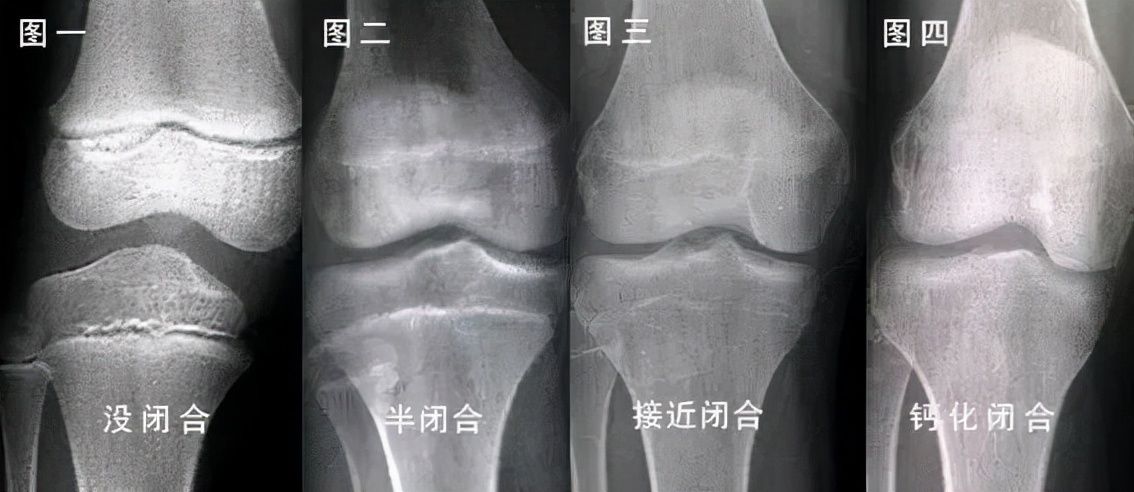

骨龄偏小的含义就在于,这证明孩子的骨骼还没有闭合,或者说闭合的时间会比较晚,那么这就意味着他们成长空间变大了,可以有更多的长高时间。因为孩子的骨骼一旦闭合,那么身高的增长基本就会停止了。如果检测显示孩子的骨龄偏大,那则说明他们骨骼闭合的时间比较早,生长空间小,长高的机会和时间有限。所以,可以见得,骨龄偏小确实是有利于长高的一种表现。